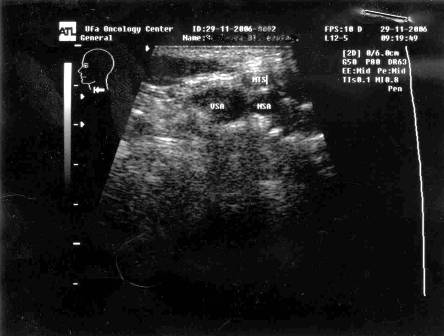

Ультразвуковое исследование лимфатических узлов шеи осуществлялось на аппарате HDI 1500 фирмы «Philips» линейным датчиком с рабочей частотой 3–5 МГц (рисунок 2).

Рисунок 2 – Сонограмма метастаза рака корня языка в прекаротидный

лимфатический узел

При дооперационном ультразвуковом исследовании использовался стандартный осмотр в В-режиме плюс методика допплерографии с изучением кровотока в лимфатических узлах.

Периферические лимфатические узлы (ЛУ) исследовали линейными датчиками с рабочей частотой 5–12 МГц. При подборе частоты датчика учитывали телосложение пациента и топографическое расположение групп исследуемых лимфатических узлов.